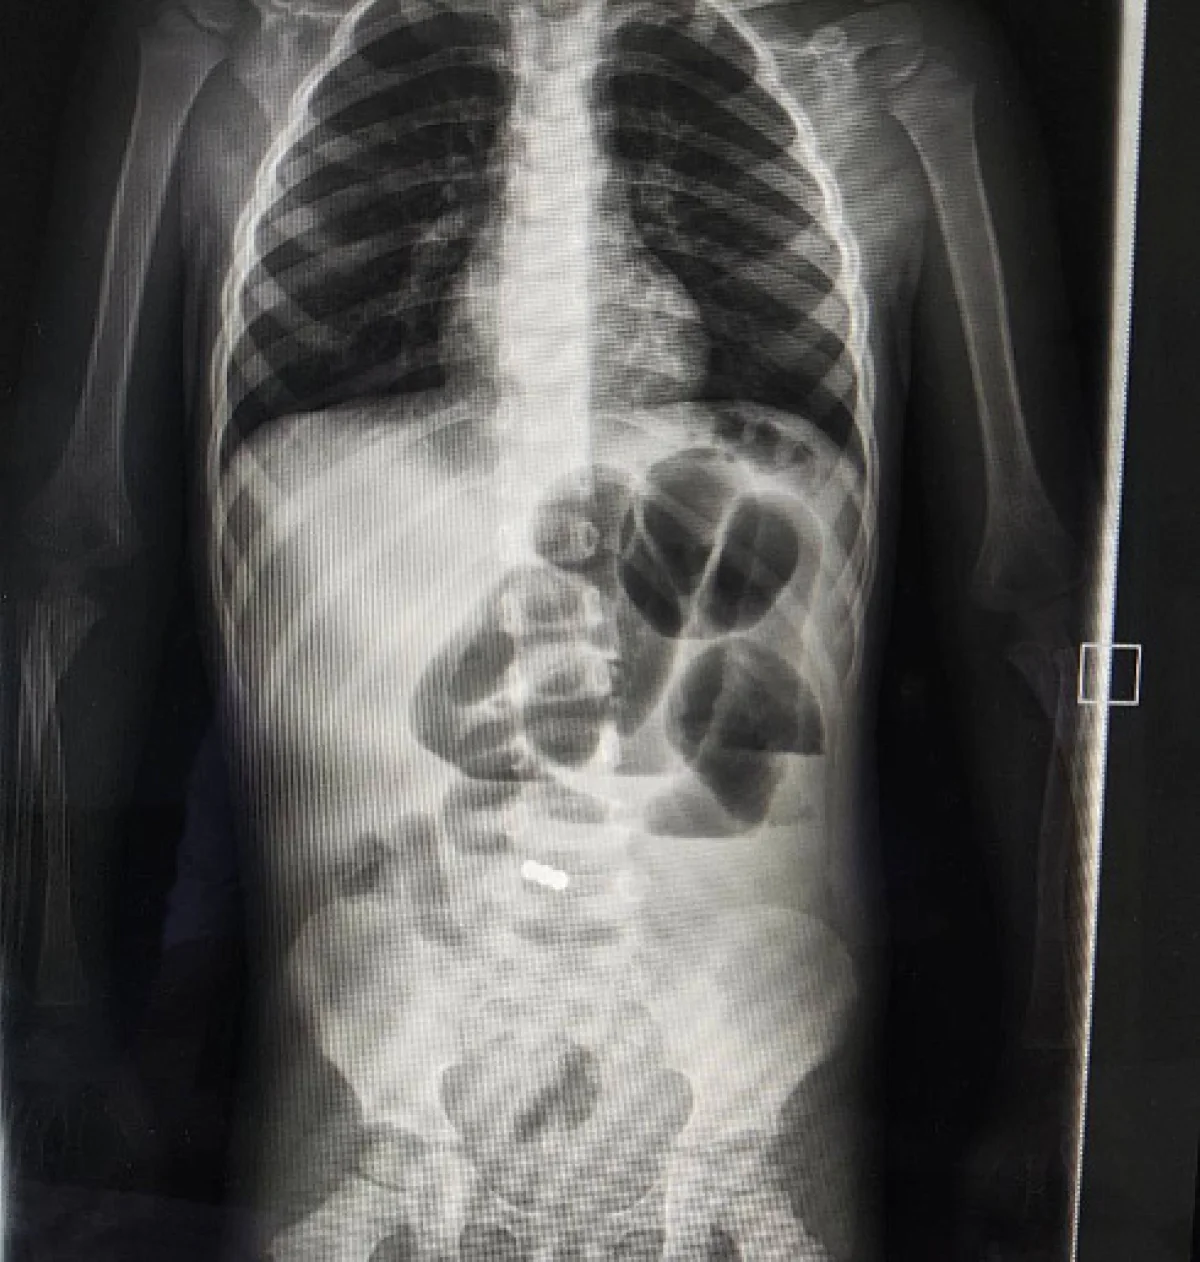

У малыша были рвота, высокая температура и боли в животе. Проведенное обследование показало наличие чуждых предметов в желудочно-кишечном тракте. Как выяснилось, это были проглоченные магниты.